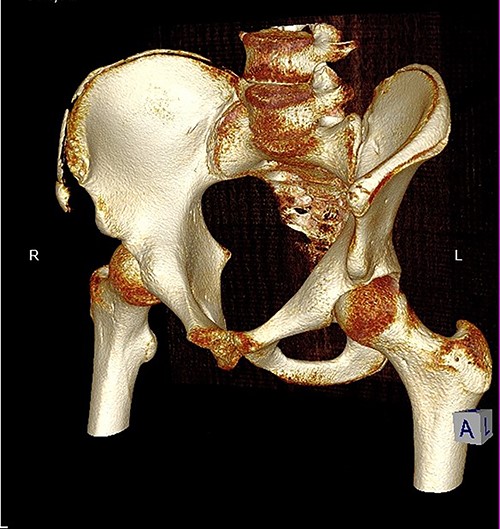

The anterior–posterior plain film X-Ray of pelvis demonstrated an avulsion fracture of the right ASIS and IC apophysis with 1.5 cm displacement (Fig. 1). Lateral view of the hip showed no extension into the joint. There was no radiological evidence of chronic overuse or previous injury. Computed tomography (CT) imaging was performed to better identify the injury; 3D volume reconstruction clearly demonstrated the unique fracture pattern of an ASIS avulsion in addition to an avulsion of the distal iliac apophysis extending ~5 cm with the described displacement (Figs 2–4).

3D reconstruction of tomographic CT scan illustrating avulsion fracture of ASIS and IC apophysis with its latero-inferior displacement (P - Posterior).